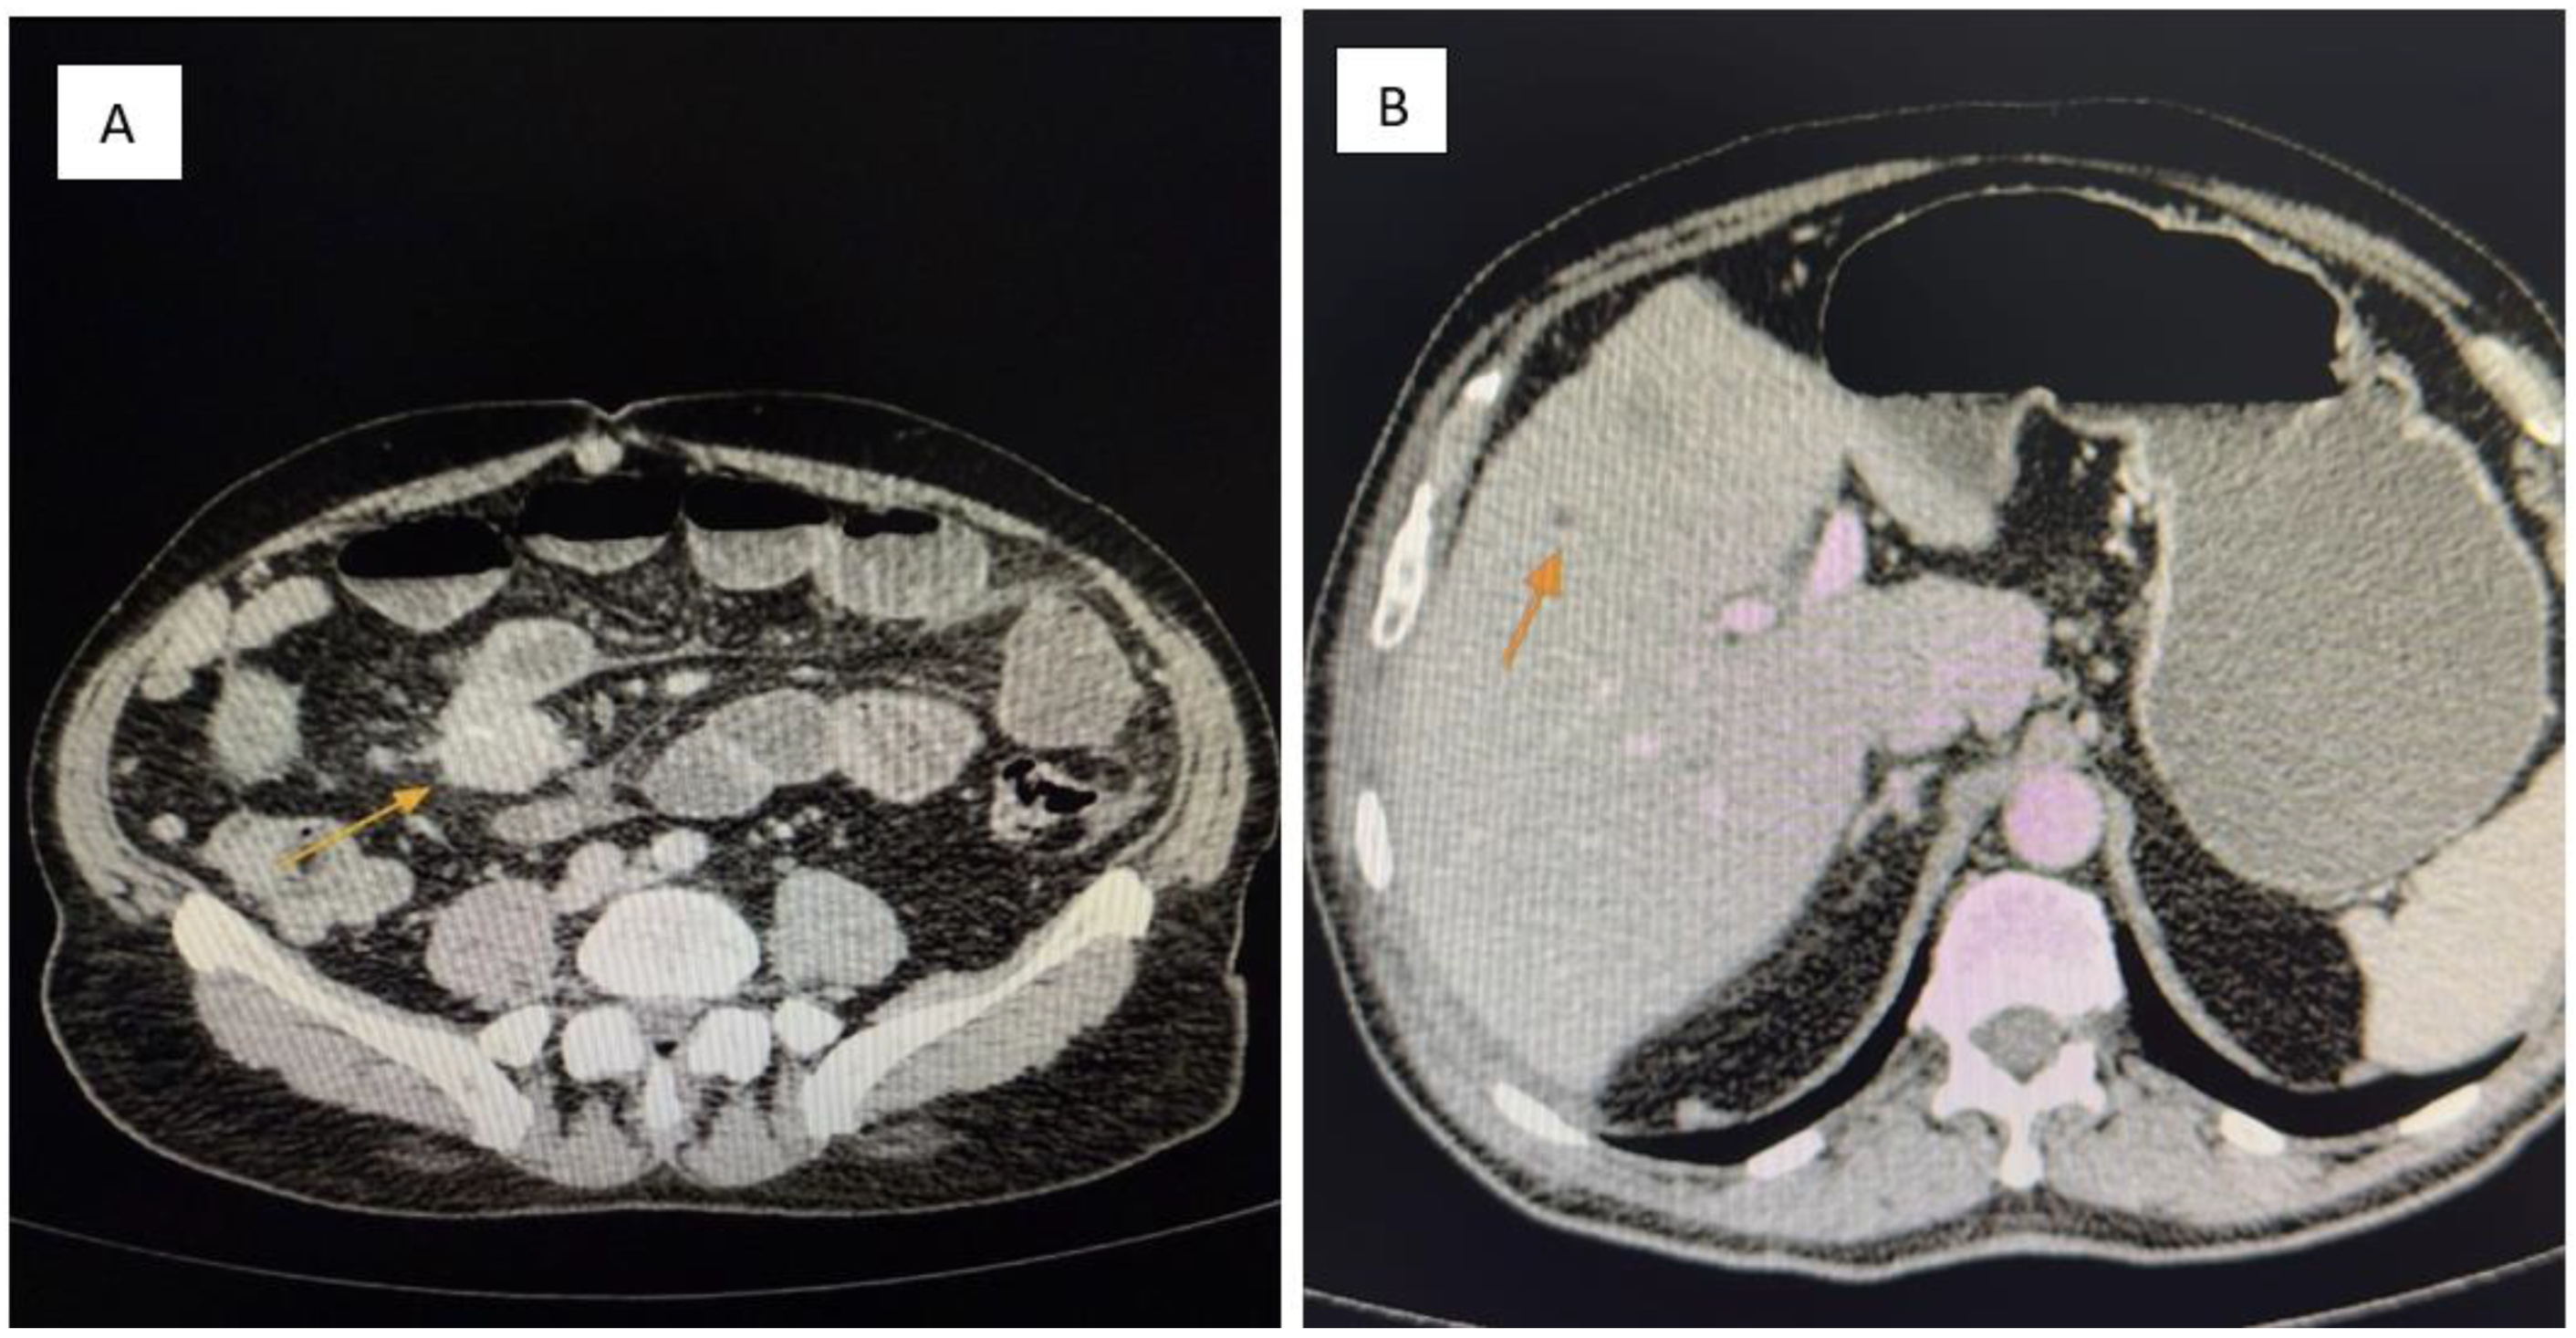

• A 5 cm mesenteric mass in the pelvic region (Figure 1A).

• Multiple hypodense hepatic nodules compatible with liver metastases (Figure 1B).

Figure 1. (A,B): Contrast-enhanced abdominal CT. (A) A pelvic mesenteric tumor mass (yellow arrow) is seen causing significant dilatation of adjacent small bowel loops, suggestive of partial obstruction. (B) Multiple hypodense hepatic lesions (yellow arrow) are visualized, consistent with secondary metastatic deposits from a neuroendocrine tumor.